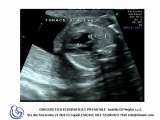

Interruzione dell'arco aortico

Coartazione dell'arco aortico

Coartazione ed ipoplasia tubulare dell'arco aortico